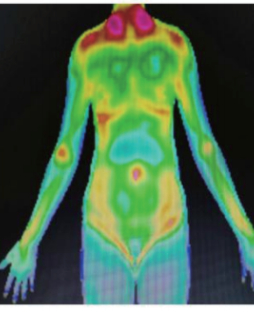

红外热图可以视为“人体健康预报云图”,对于亚健康人群,红外热成像技术检测是适宜的评估技术。

红外热成像技术可以将中医学抽象的阴阳、寒热等概念可视化、图像化,用于评估人体阴阳平衡的变化,辨识证候的阴阳、寒热,具有不接触、无辐射、无创伤、快速方便等特点,在治未病健康评估、疾病预警、干预效果评估等方面广泛应用,展现出良好的应用前景。

大量文献报道证实了这一点,潘跃红等选取50例均处于亚健康状态的人群,对调理前后的红外热成像图进行对比与分析,结果显示治疗后的亚健康人群的症状和红外热图的温度差值基本吻合,表明红外热成像技术应用于亚健康状态是可行的。